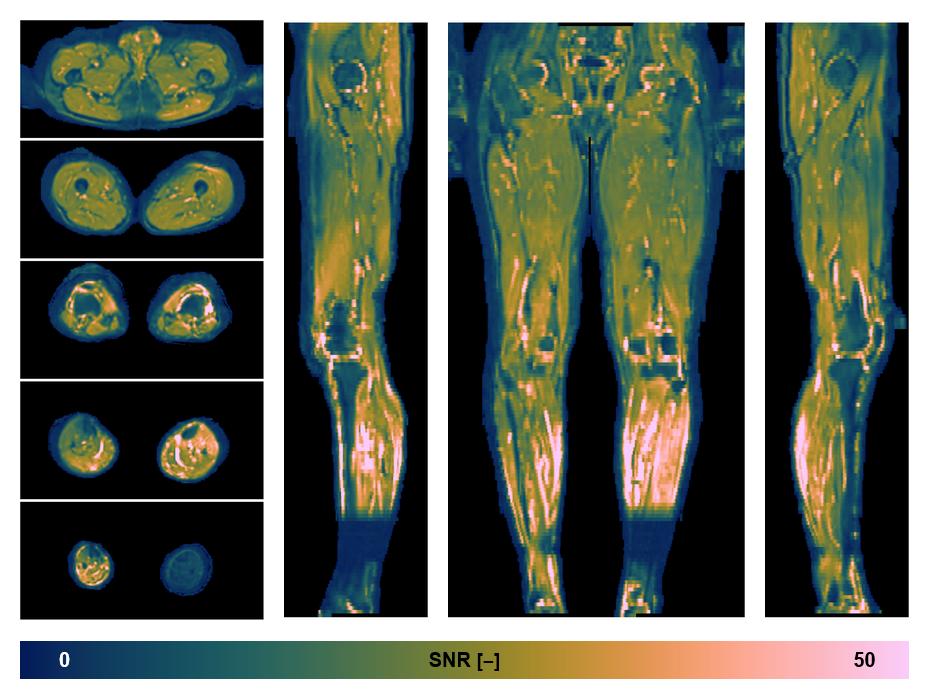

• SNR of the unweighted image

SNR distribution of the unweighted diffusion data.